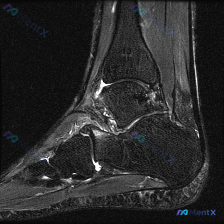

这是一张膝关节矢状位T1加权MRI影像,图像对比度尚可,解剖结构清晰,无明显运动伪影,层面接近膝关节中间矢状面,完整显示股骨远端、髌骨、膝关节间隙及胫骨近端结构。

- 骨骼结构:股骨、胫骨骨髓信号正常,骨皮质连续光滑,无骨质中断、骨赘形成,软骨下骨板完整,关节对位正常,无脱位半脱位。

- 关节内结构:

- 关节软骨:股骨髁、胫骨平台关节面软骨覆盖连续,未见明确剥脱或全层缺损

- 半月板:形态完整,信号均匀低信号,无明显撕裂征象

- 交叉韧带:前后交叉韧带走行连续,信号正常,无中断或增粗扭曲

- 周围软组织:髌上囊及周围脂肪信号均匀,无异常积液或肿块

- 初步结论:这一T1矢状位层面未发现明显骨质破坏、骨折、韧带断裂、严重半月板撕裂或关节积液等病理改变。